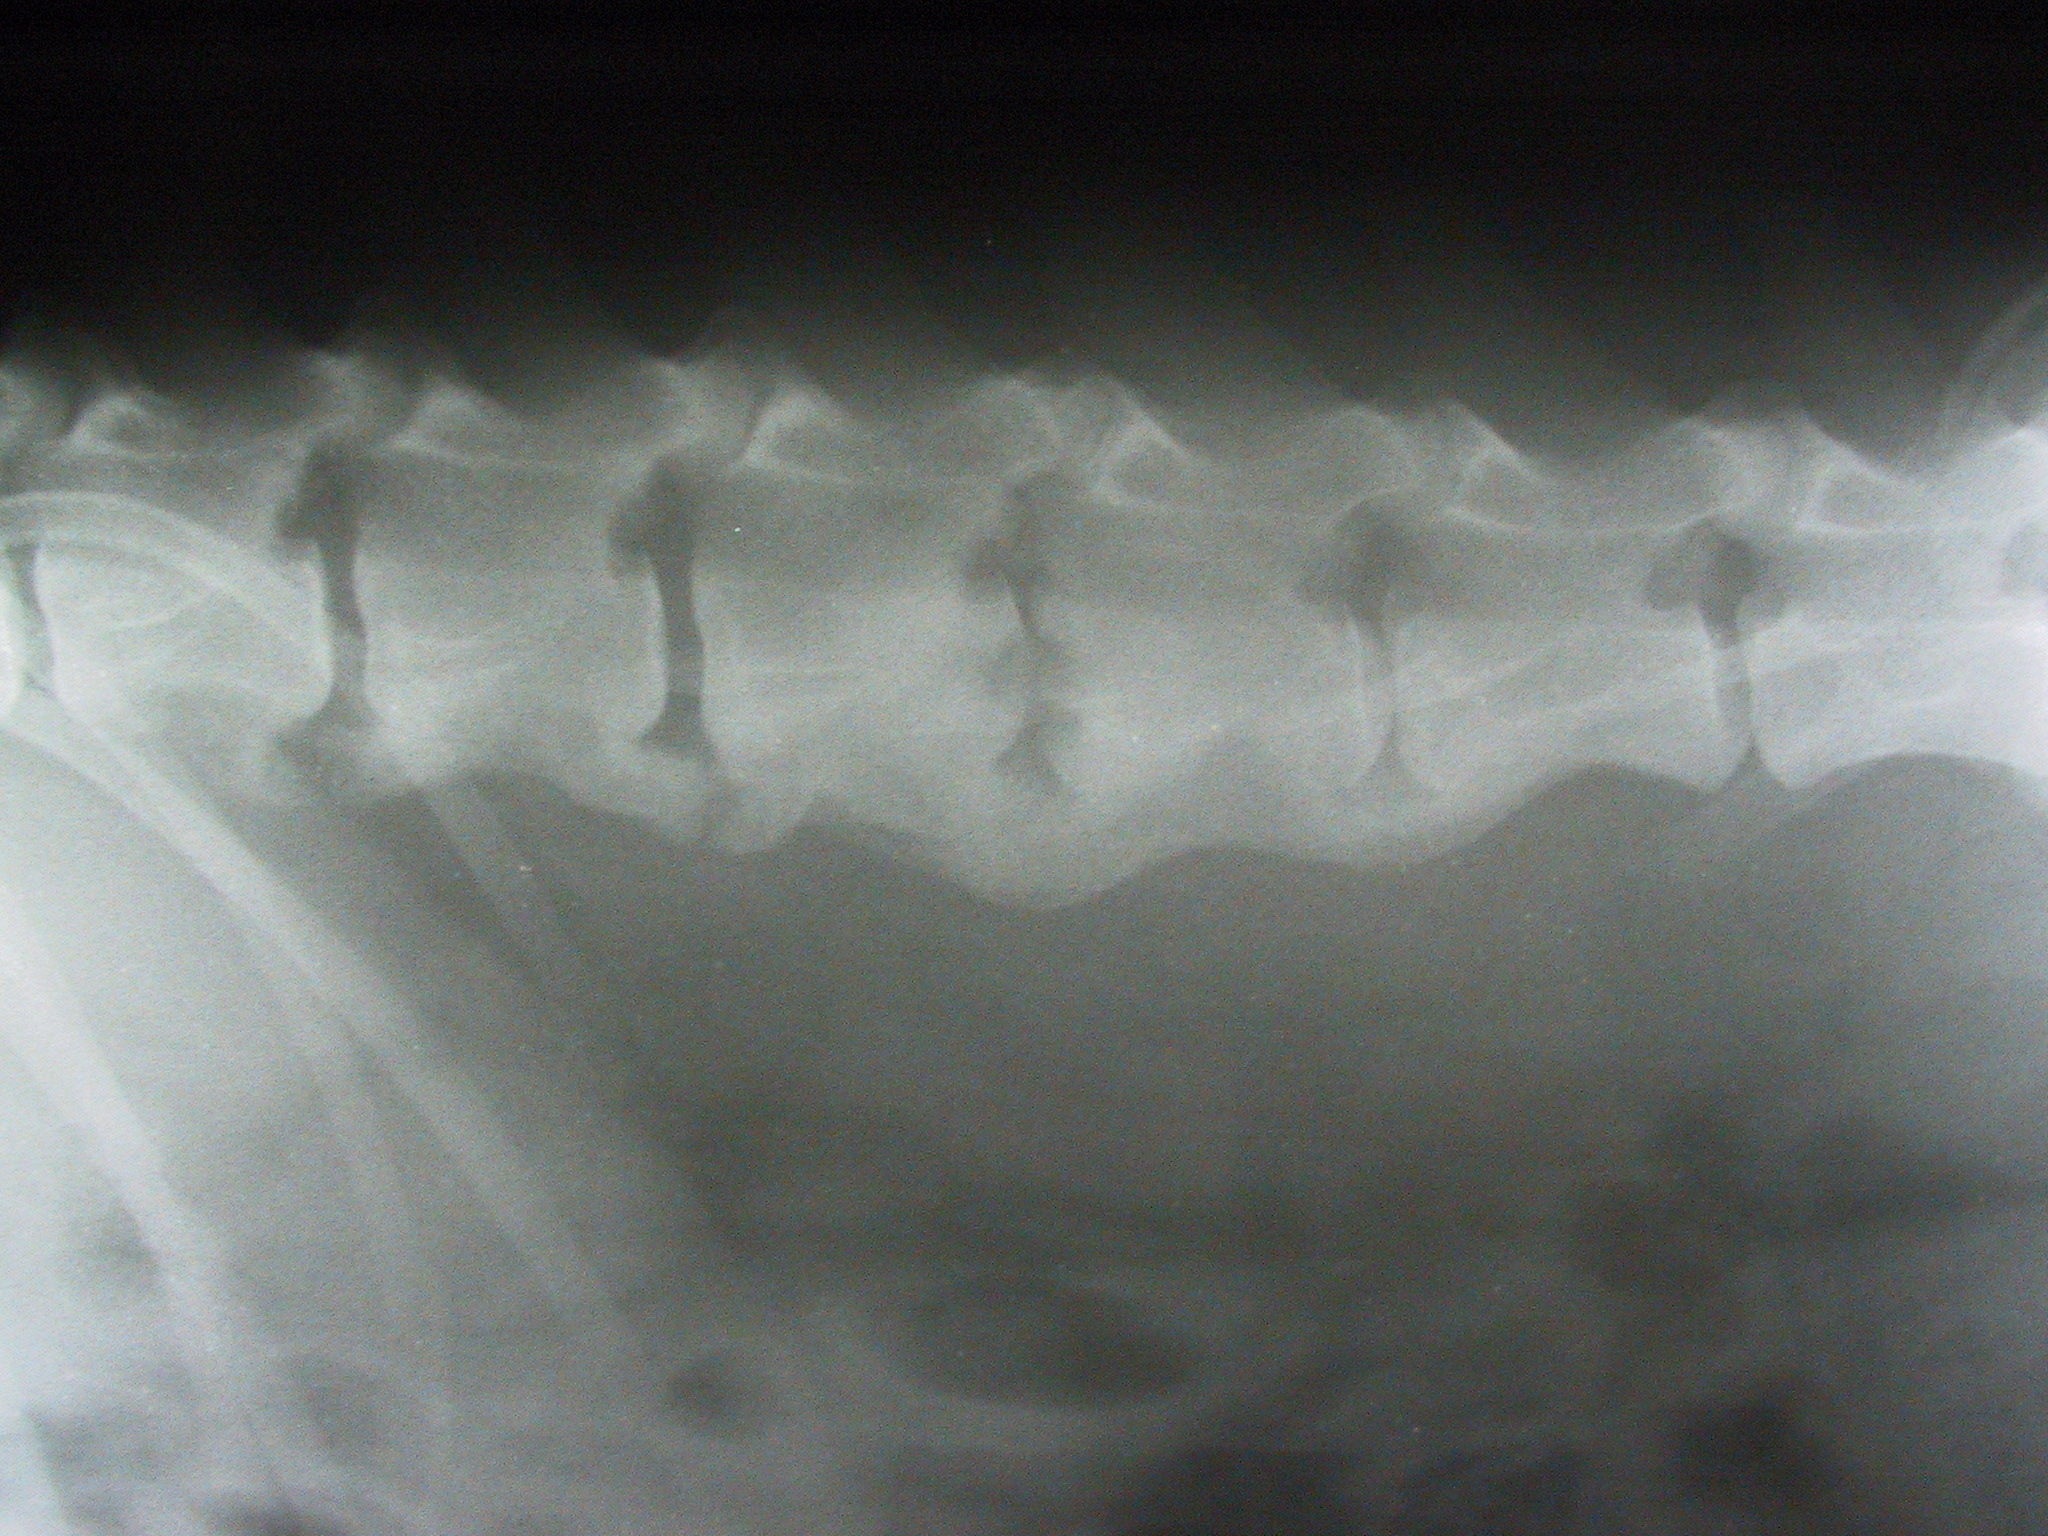

Spondyloarthrosen, Diskospondylitis Zurück